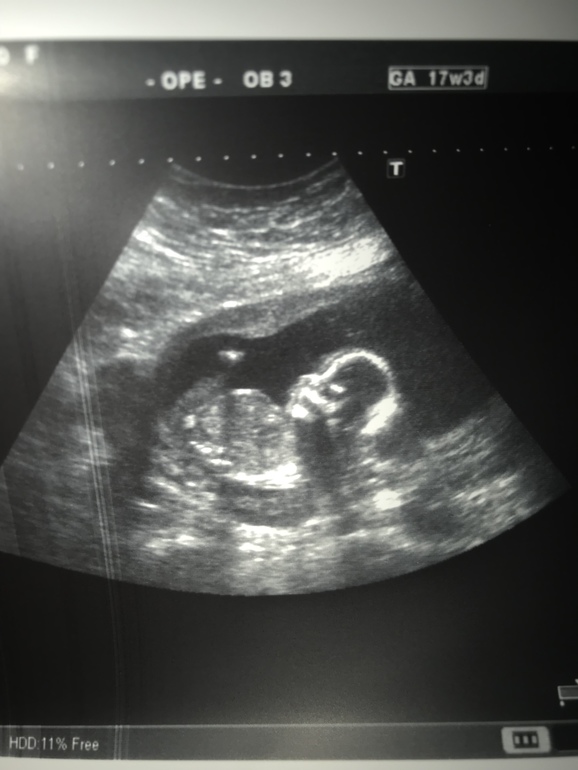

Узи в 17,3 и пол)

УЗИ, КТГ, доплерВот и сходили мы на узи))

Все у нас замечательно 178 грамм весит наша пуговка и предположили .... мальчика)))) моя интуиция меня не подвела))) будет у нас Ванечка))))

Сказали плацента 1,4 см и это на 17,3 недели... надеюсь поднимится((((( а так все прекрасно лежал спинкой к нам и зевал)))) утомили сыночка)))) была у врача много набрала, здравствуй гречка и кефир(((( общее самочувствие на 3йку низ живота переодически болит, и голова... вот сейчас пишу а виски как в тисках но это наверно погода(

И фоточка на память)